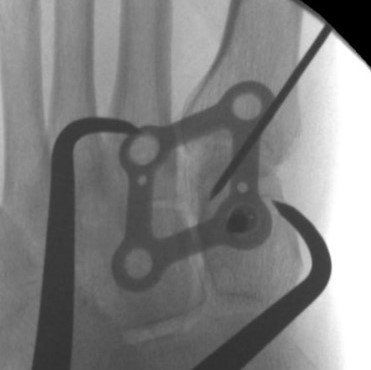

This surgical procedure involves reducing the midfoot joints and holding them stable until healing occurs.

Strong suture material (Arthrex Lisfranc Internal Brace) or a plate and screws is inserted. The pattern of injury determines what is used.

Plate fixation is stronger than suture fixation but requires plate removal 4 to 6 months after insertion.